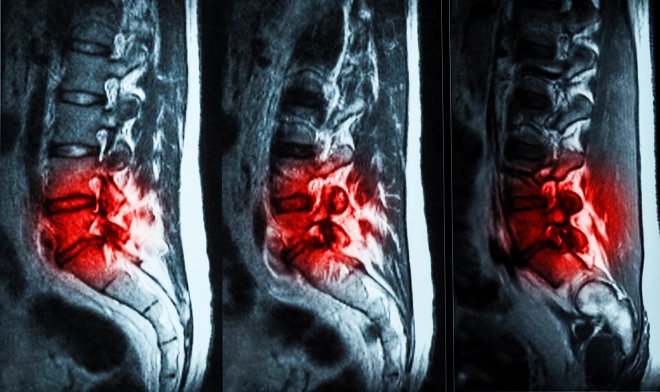

Специально разработанный гидрогель устранит поясничные боли

Американская компания ReGelTec представила собственную разработку гидрогеля Hydrafil, который может навсегда решить проблему поясничной боли. Средство вводится в позвоночник в те места, где диагностированы травмы и трещины поврежденных дисков. В итоге гидрогель частично восстанавливает утраченную амортизацию и снимая боль. На сегодняшний день пациенты 22-69 лет в количестве 20 добровольцев участвуют в испытании средства.

Процесс заключается в следующем: нагретый гель становится густым, после чего вводится при помощи шприца в пораженные диски. Средство охлаждается до температуры тела, в результате чего формируется имплантат. По характеристикам он практически не уступает межпозвоночному диску человека. После введения средства пациент полгода еще наблюдается у врача.

Испытуемые уже отметили пользу препарата по 10-бальной шкале: снижение болевых ощущений с 7,1 до 2,0, а уменьшение боли, которая мешает заниматься повседневной деятельностью, - с 48 до 6.